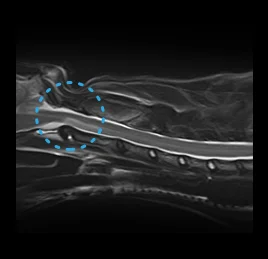

• 허혈성 척수병증

• 척수공동증

• 디스크 탈출증

• 척수 질환

디스크 탈출증, 척수염, 허혈성척수병증,

척수공동증, 척수종양, 척추 기형